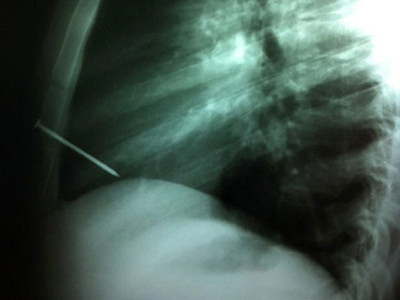

Kết quả chụp X-quang cho thấy chiếc đinh đã đâm thẳng vào khoang tim của bệnh nhân. Sau 2 tiếng phẫu thuật, các bác sĩ mới lấy được chiếc đinh ra.

| Ảnh chụp X-quang chiếc đinh đâm vào tim người thợ mộc. Ảnh: Nydailynews. |

Kết quả chụp X-quang cho thấy chiếc đinh đã đâm thẳng vào khoang tim của bệnh nhân. Các bác sĩ đã tiến hành phẫu thuật và lấy chiếc đinh ra khỏi lồng ngực sau 2 tiếng.